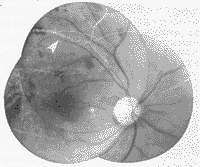

例3 女,16岁,主诉军训后疲乏,双眼视物不清一周。于1996年10月3日来眼科门诊检查,视力双眼0.1,眼前节正常。散瞳检查眼底:视乳头色稍淡尤以颞侧明显,边界清楚,黄斑水肿,动脉稍细,静脉扩张纡曲,后极部视网膜散在大量棉絮样斑无出血(图3,4)。疑为胶原血管性眼底病变,转内科检查。全身检查:血压130/90 mmHg,双侧面颊对称性红斑,红细胞沉降率44 mm/1h,抗核抗体阳性,血清球蛋白增高为44 g/L,肝功异常,诊断:SLE。1997年12月29日门诊追踪检查,视力右眼0.05,左眼0.1,双眼前节正常。眼底右眼视乳头色苍白,边界清楚,黄斑中心凹光反射消失,色素沉着,视网膜动静脉细有白鞘,从视乳头上有新生血管机化膜并沿四支大血管走行。视网膜后极部有少量点状出血(图5)。左眼视乳头色淡白,边界清楚,黄斑中心凹光反射消失并往上移位。动脉细有白鞘,静脉血管纡曲管径粗细不匀,并有新生血管膜形式。视网膜散在点片状出血(图6)。FFA双眼动静脉血管管径细,粗细不匀晚期管壁染色,视网膜周边3600均有大片毛细血管闭塞区, 呈现弱荧光。围绕视乳头3600距视乳头0.5~8.0 PD范围有大量新生血管,呈现多簇大小不等的强荧光团(图7,8)。诊断:双眼SLE视网膜血管炎合并新生血管;视神经萎缩。嘱查视野并作激光光凝,但患者家在农村未再复诊。

图3,4 例3患者双眼眼底普通像。后极部视网膜大量棉絮样斑 图5 例3患者右眼眼底彩色像。视盘色苍白,从视盘上有新生血管机化膜沿四支大血管走行 图6 例3患者右眼眼底彩色像。视盘色淡白,后极部视网膜有多数新生血管形成 图7 例3右眼眼底荧光血管造影像。视网膜周边部大量无灌注区,围绕视盘有大量新生血管产生的荧光素渗漏 图8 例3左眼眼底荧光血管造影像。视网膜周边部大量无灌注区,后极部多数新生血管渗漏,下方有视网膜前出血(箭头)